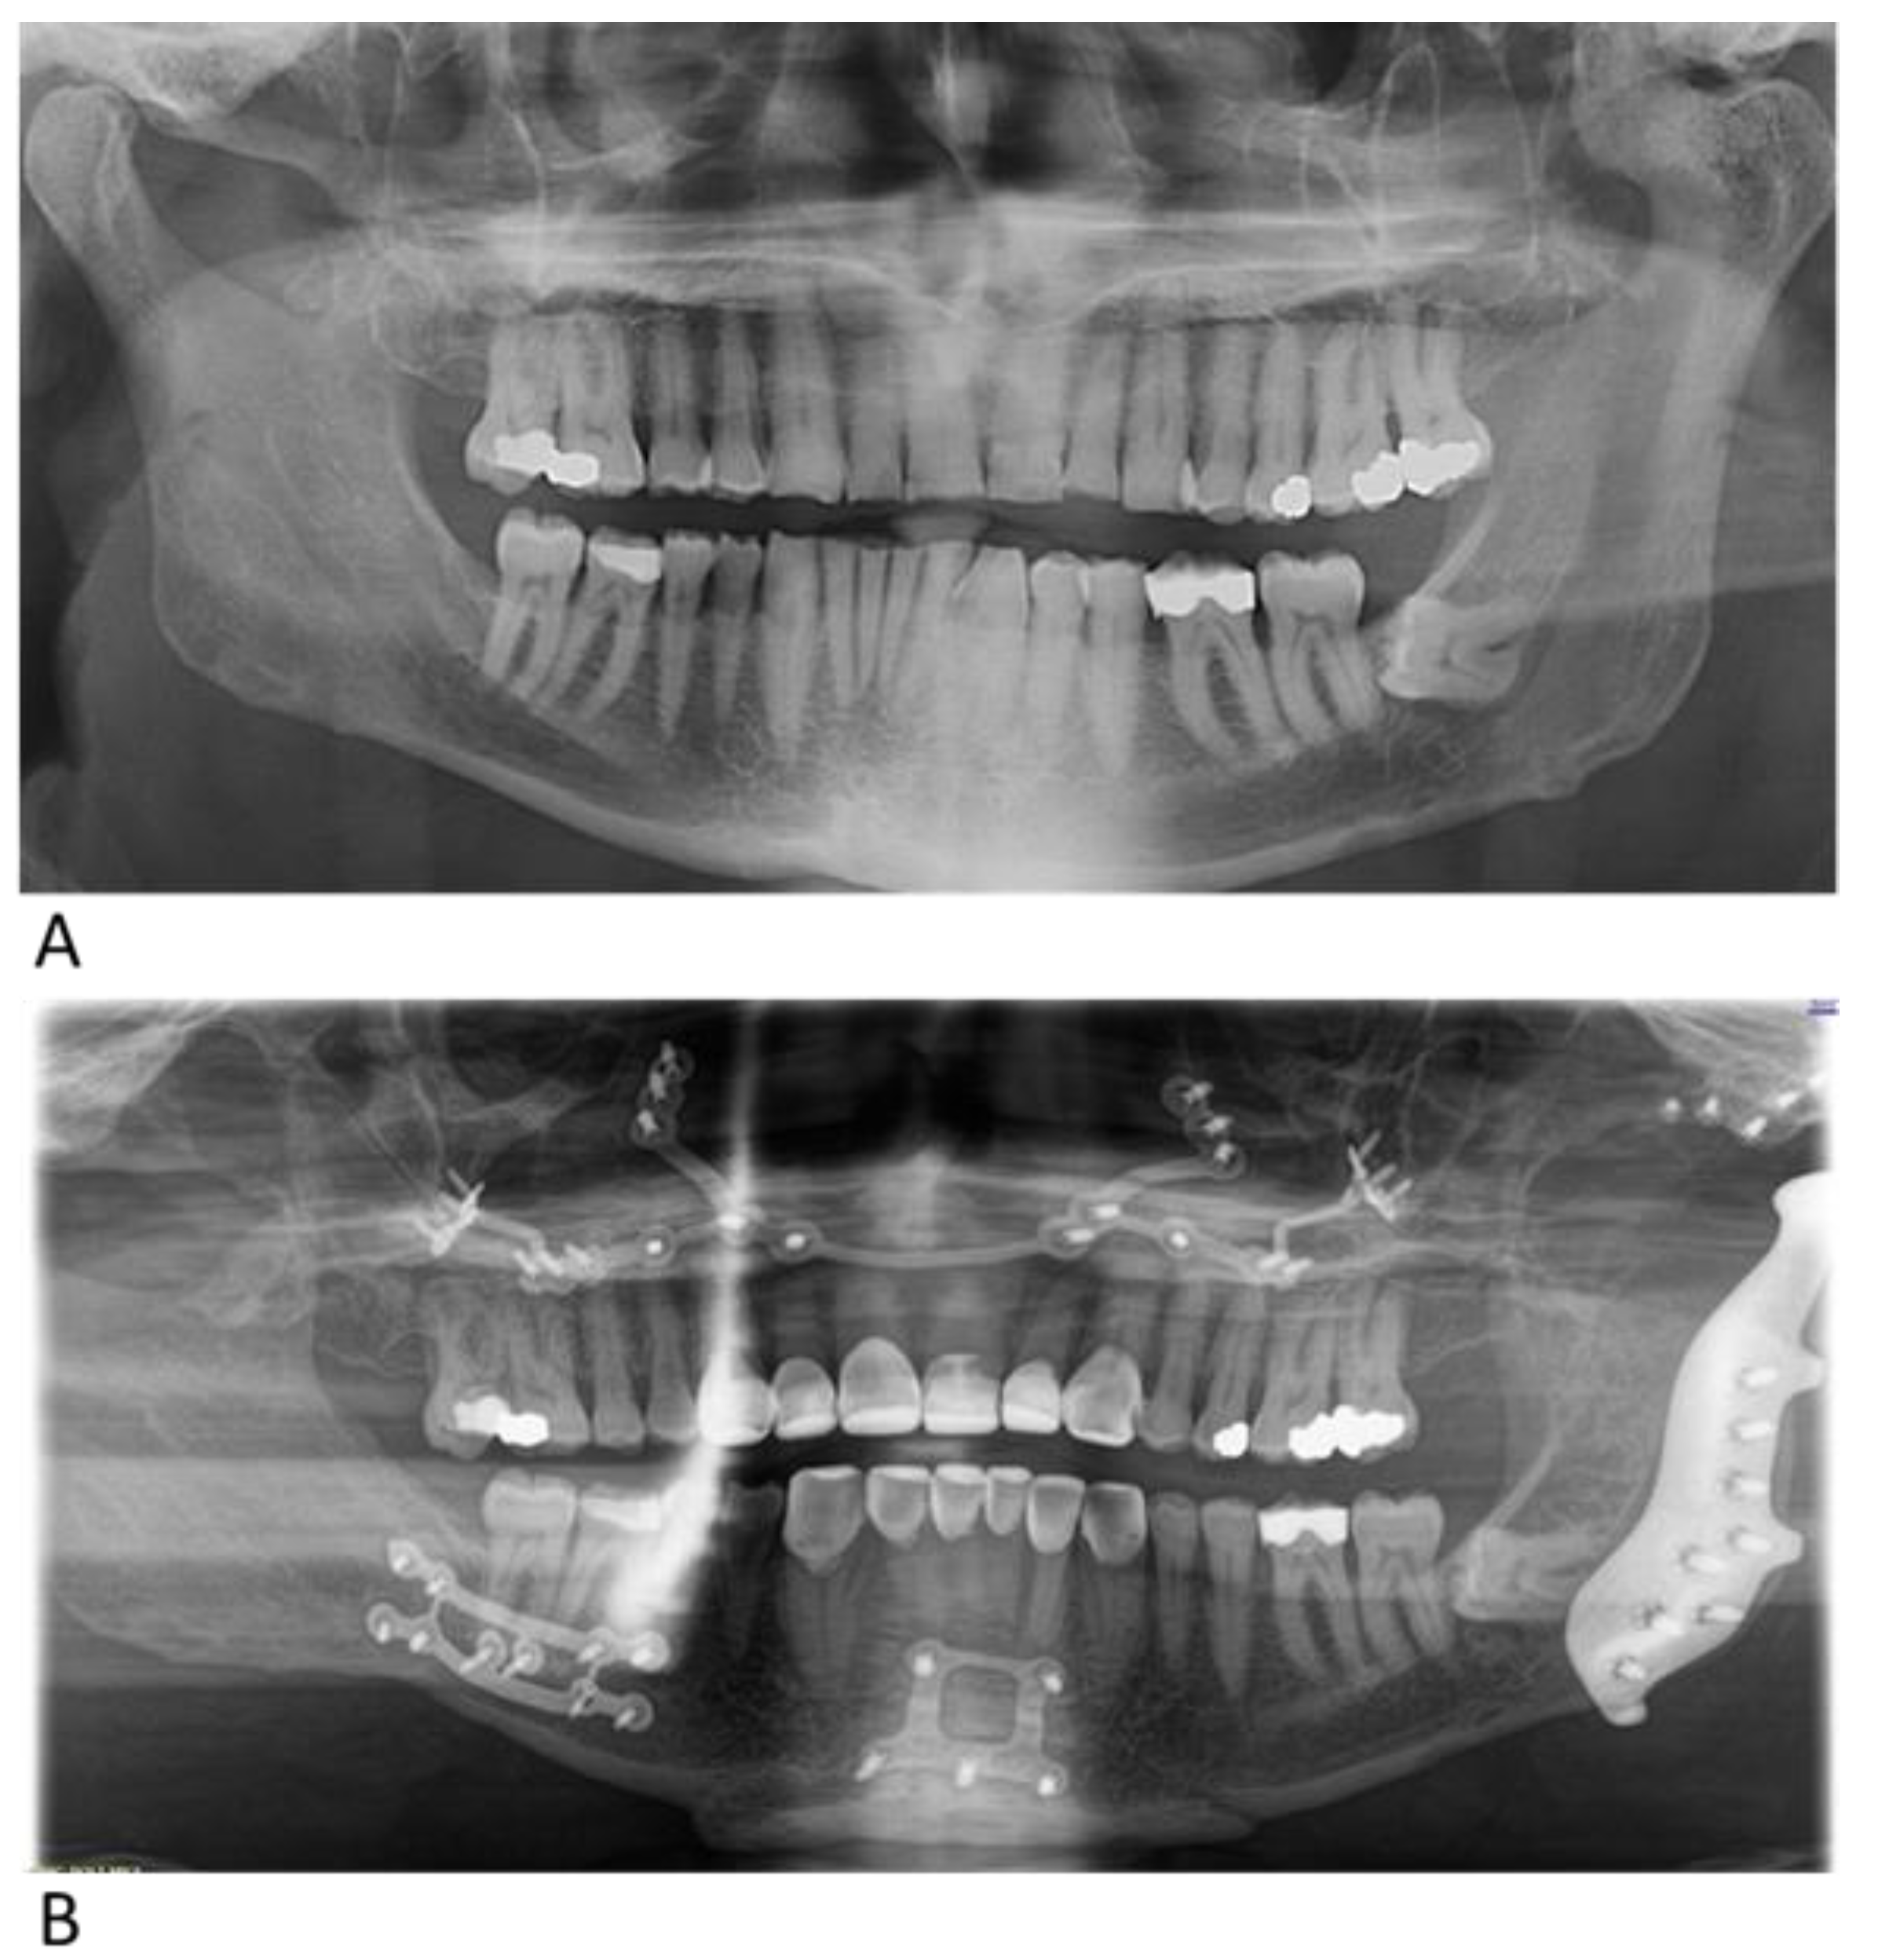

3. Case Report

3.1. Case 1

3.2. Case 2

3.3. Case 3